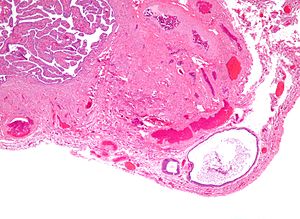

A cystic Walthard cell rest of the fallopian tube. H&E stain.

LM collection of eosinophilic (i.e. pink) cuboidal cells - usually solid, may be cystic; elliptical nucleus with single groove along major axis - "coffee bean" nucleus

• Collection of eosinophilic (i.e. pink) cuboidal cells; usually solid, may be cystic.

• Elliptical nucleus with single groove along major axis; "coffee bean" nucleus -- key feature.

• Usually in soft tissue of the uterine tube.